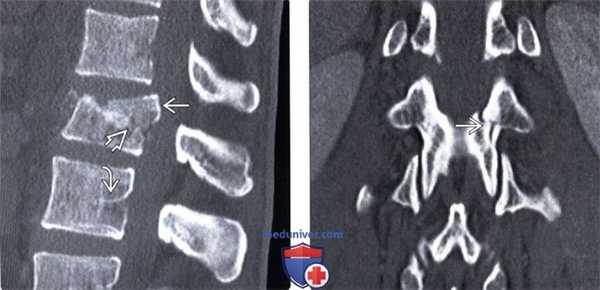

(Слева) КТ, сагиттальный срез: взрывной перелом тела L1 позвонка со смещением задней покровной пластинки в спинномозговой канал. Линия перелома продолжается на заднюю сосудистую бороздку. Нормальная сосудистая бороздка отличается от перелома ровными контурами и характерной локализацией.

(Справа) На фронтальном КТ-срезе этого же пациента виден вертикальный перелом межсуставной части дуги. Это характерное для компрессионного механизма травмы повреждение, отличающееся от горизонтального перелома задних элементов при флексионно-дистракционных повреждениях.